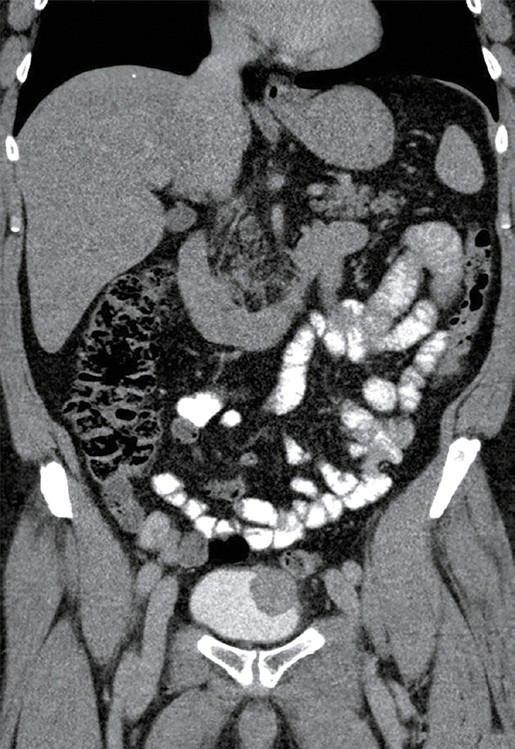

Inflammatory myofibroblastic tumors (IMTs) of the bladder are rare, with a limited number of cases reported in the literature. Complete resection with negative margins is essential to reduce the risk of recurrence, while bladder function preservation is also crucial for the patient. This study describes a 56‑year‑old patient with a bladder dome IMT managed using robot‑assisted partial cystectomy facili‑ tated by perioperative cystoscopic tattooing to precisely demarcate the tumor margins. The procedure began with cystoscopic tattooing of the lesion using Black Eye dye, followed by robotic resection with the da Vinci Xi system. Complete transmural resection and a 2‑layer bladder closure were performed, with preservation of the bladder capacity. The patient experienced minimal blood loss, no intraopera‑ tive complications, and was discharged 2 days after the procedure. Follow‑up examinations, including cystoscopy and computed tomography, confirmed no recurrence 12 months after surgery. Cystoscopic tattooing facilitated clear intraoperative tumor localization, enabling precise resection and minimal bladder wall loss. This approach addressed a key challenge of robotic bladder surgery-lack of tactile feedback-while maintaining functional outcomes. Robot‑assisted partial cystectomy with cystoscopic tattooing represents a promising alternative to maximal transurethral resection, especially in the context of bladder‑sparing trimodal therapy, for patients who are not eligible for or unwilling to undergo radical cystectomy. This technique is particularly relevant given the increasing focus on minimally invasive procedures and advancements in systemic therapy. In the future, this method could be adapted for ureteral robotic surgeries to enhance lesion localization.

膀胱炎性肌纤维母细胞瘤(IMTs)较为罕见,文献报道的病例数量有限。切缘阴性的完整切除对于降低复发风险至关重要,同时保留膀胱功能对患者也至关重要。本研究描述了一名56岁患有膀胱顶部IMT的患者,采用机器人辅助部分膀胱切除术进行治疗,术中通过膀胱镜纹身精确界定肿瘤边缘。手术首先使用“黑眼”染料对病变进行膀胱镜纹身,然后使用达芬奇Xi系统进行机器人切除。进行了全层切除和两层膀胱缝合,保留了膀胱容量。患者术中出血极少,无术中并发症,术后2天出院。包括膀胱镜检查和计算机断层扫描在内的随访检查证实,术后12个月无复发。膀胱镜纹身有助于术中清晰定位肿瘤,实现精确切除并减少膀胱壁损失。这种方法解决了机器人膀胱手术缺乏触觉反馈这一关键挑战,同时维持了功能效果。对于不符合根治性膀胱切除术条件或不愿接受根治性膀胱切除术的患者,机器人辅助部分膀胱切除术联合膀胱镜纹身是最大经尿道切除术的一种有前景的替代方法,特别是在保留膀胱的三联疗法背景下。鉴于对微创手术的日益关注和全身治疗的进展,该技术尤为重要。未来,这种方法可应用于输尿管机器人手术以增强病变定位。